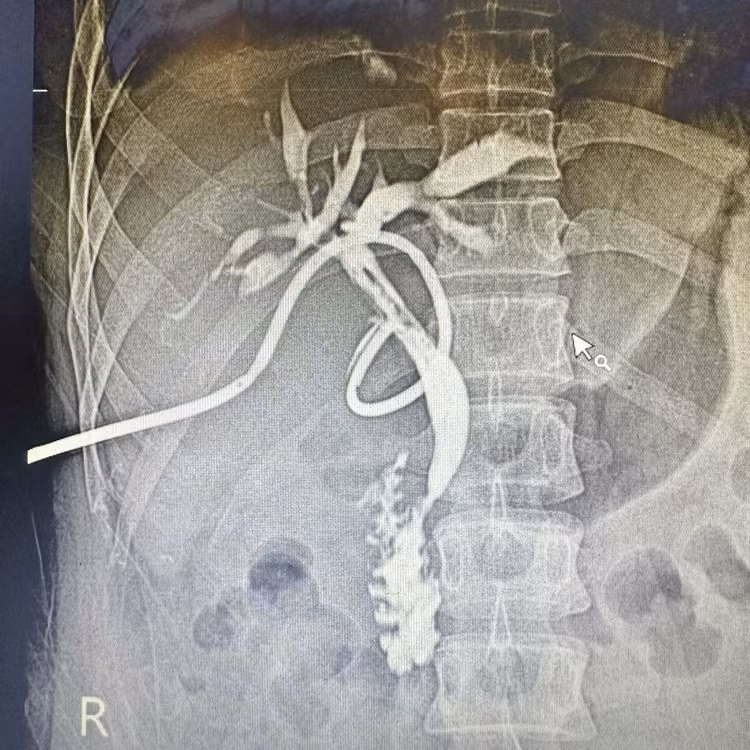

Trong quá trình phẫu thuật, thông qua hệ thống nội soi đường mật ống mềm, các bác sĩ đã tiếp cận các nhánh đường mật trong gan, xác định vị trí sỏi và tiến hành tán sỏi bằng laser, sau đó lấy hết các mảnh sỏi ra khỏi đường mật. Kết quả chụp kiểm tra sau mổ cho thấy hệ thống đường mật lưu thông tốt, sạch sỏi.

Phim chụp kehr sau mổ cho thấy đường mật đẹp, sạch sỏi - Ảnh BVCC